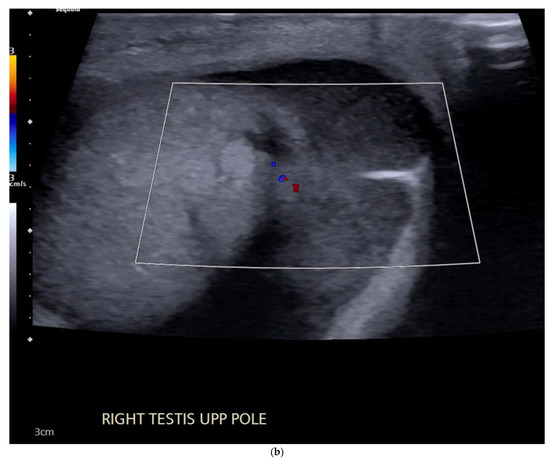

4.1. Seminomatous Germ Cell Tumour

| Seminomas | Homogenous and hypoechoic Well circumscribed Occasionally contain cystic components or calcifications |